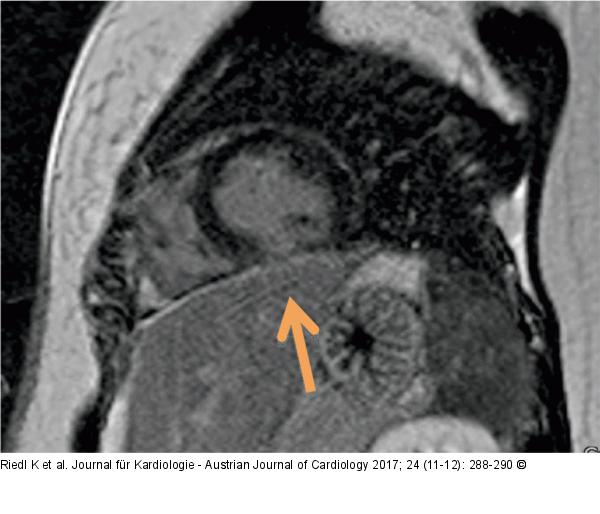

Abbildung 5: Late-Enhancement

Late-Enhancement inferior basal (PSIR, Short axis) |